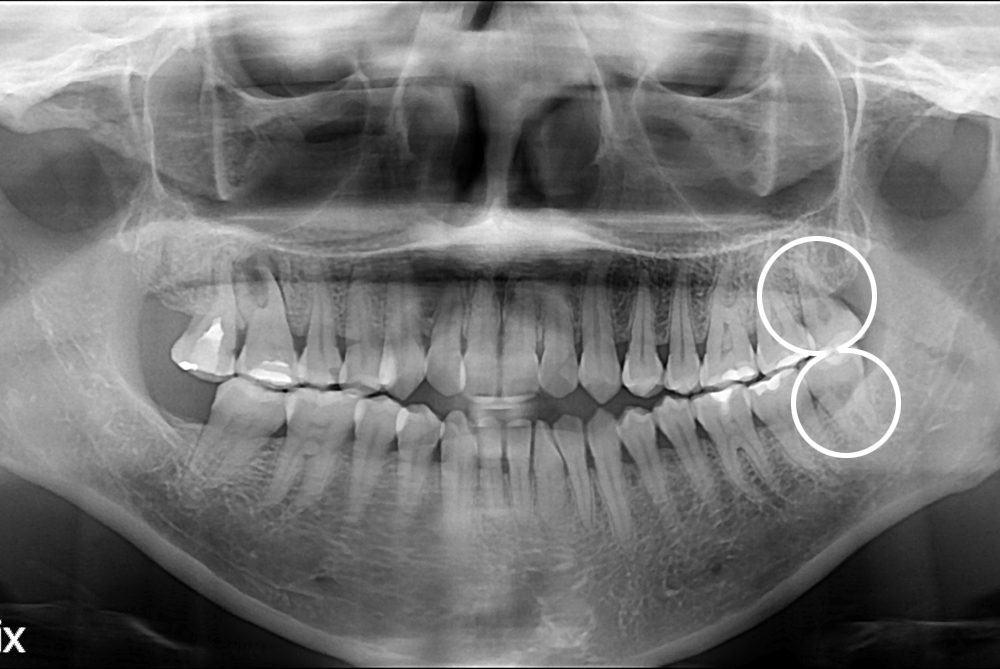

치료사례

세종치과의 진심 어린 치료는 결과로 말합니다.

실제 내원하신 환자분들의 치료 전·후 사례를 확인해보세요.

모든 치료사례 전후사진은 환자분의 동의하에 촬영되었습니다.

모든사진은 동일 환자분의 전후모습을 촬영하였으며, 사진의 밝기조절 외에 임의 수정이 없음을 알려드립니다.